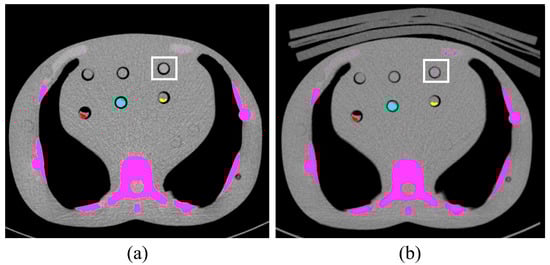

2. Materials and Methods

2.3. Image Analysis

2.4. Phantom Study

2.5. Calcium Scoring

3.1. Patient Study

3.2. Phantom Study